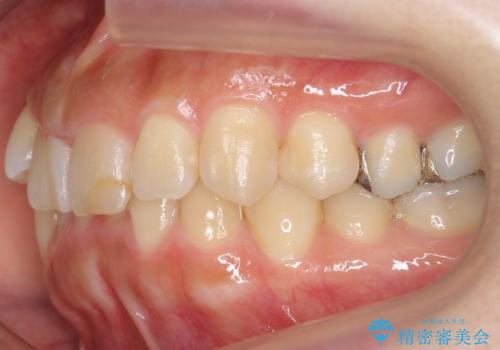

前歯(犬歯)の反対咬合は改善はインビザラインですと時間がかかるため、ワイヤー矯正で短期間で入れ替えるほうが、患者様の負担が少なくて済みます。

入れ替える期間は前歯しか当たらない状態になり、大変食事もしにくくなるうえ、前歯にも負担がかかります。ワイヤーは少々目立ちますがおすすめです。